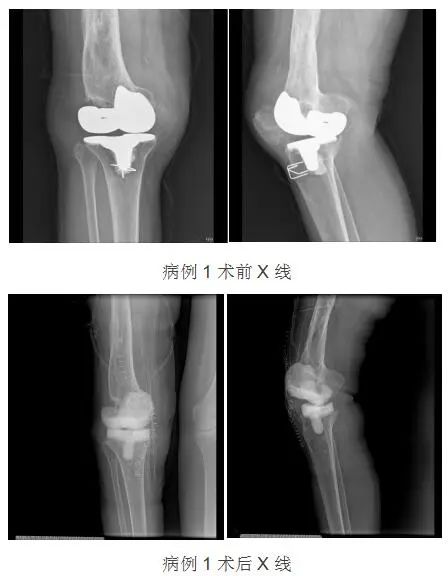

病例1:

病例1:女性,62岁,因“扭伤致右膝关节肿胀疼痛,活动受限3天”来诊。X片显示:右膝关节假体松动。8年前因“右膝骨关节炎”行人工全膝关节置换术,4年前行右膝外侧副韧带损伤重建术。

此后,徐兵主任团队为病例1中患者实施了“膝关节假体取出+病灶清除术+骨水泥占位器植入+膝关节旷置术”,打开膝关节腔后,可见关节腔内、髌上囊及股骨远端大量脓液,股骨髁及胫骨托假体松动,聚乙烯衬垫严重磨损破碎,术中予以取出假体,彻底扩大清除病灶,取出病灶培养组织送检,彻底冲洗,安装骨水泥间隔器。术后规范使用抗生素抗感染。